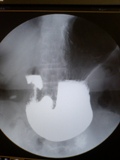

UGI

II-CCD-DR.UGIexaminationKnowHow

1 2 3 4 5 xtvugitecingrish hokenkyoukaiUGIsetumeiSiryou HousyasengyoumutejyunnMRI signa0 DRXTVugi

DRXTVugi (2) DRugitecnology DRugiknowhow

胃エックス線二重造影初歩の初歩